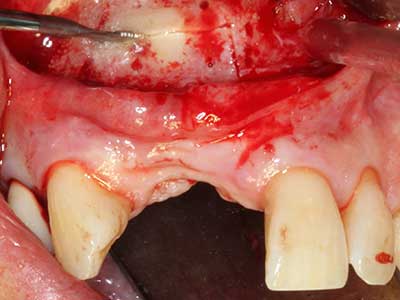

Fig. 21: Defecto extendido del incisivo superior con indicación para osteogénesis de distracción con tejido blando cicatrizado después de una operación previa.

Fig. 22: El segmento móvil puede separarse de forma precisa con la delgada sierra para osteotomía (Piezomed de W&H).

Fig. 23: Movilización final del segmento de distracción palatinal pedicular con el cincel.

Fig. 24: Incorporación del distractor (sistema TRACK, KLS Martin).